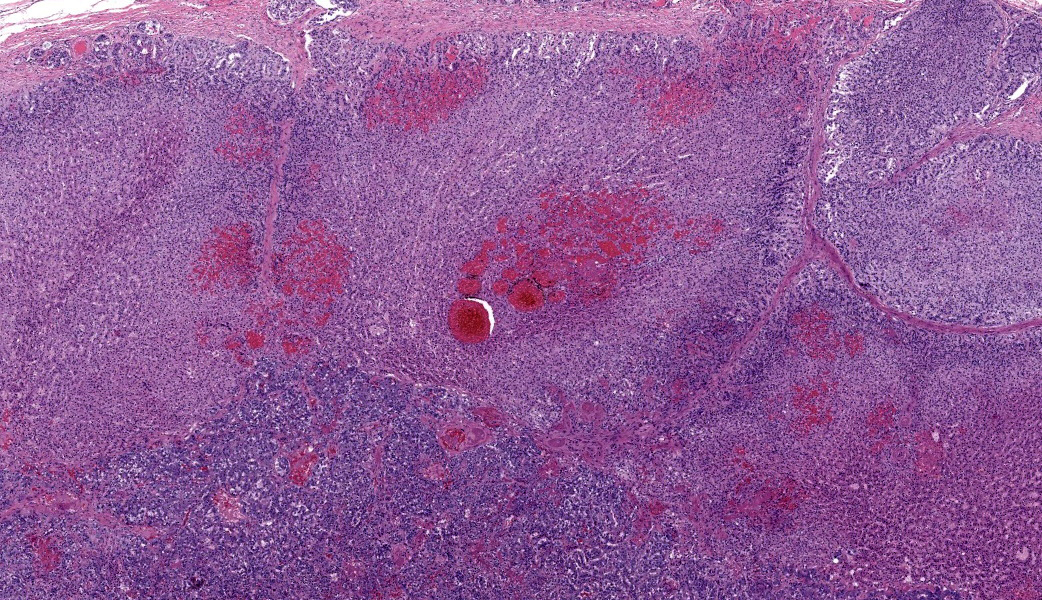

Adrenal glands: Multifocally, the small arteries and arterioles within the cortex and medulla show marked thickening of their walls, and narrowing or obliteration of their lumen, by intramural deposition of plasma proteins (consistent with hyaline arteriolosclerosis). Some vessels show intramural laminar deposits of plasma proteins (onion-skinning). Many sinusoidal vessels in the medulla are occluded by fibrin thrombi and are frequently effaced by hyaline material.Contributor's Morphologic Diagnoses:

Adrenal glands: Multifocal hyaline arteriolosclerosis.Condition: Hypertensive vasculopathy. Other diagnoses (tissues not included in the submission):